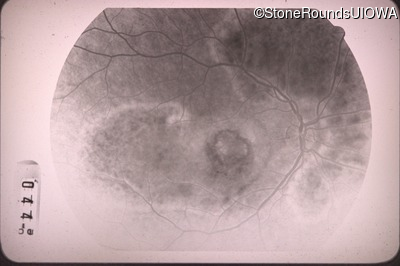

Fluorescein Angiography - Right - 20/100 -1

Exemplar